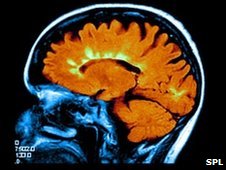

Rúmlega 55% MS-sjúklinga reyndust vera með æðaþrengsli í heila að því er fram kemur í nýrri rannsókn á 500 sjúklingum, sem tóku þátt í rannsókn sem gerð var við Háskólann í Buffalo. Frá þessu var greint í fréttum á d